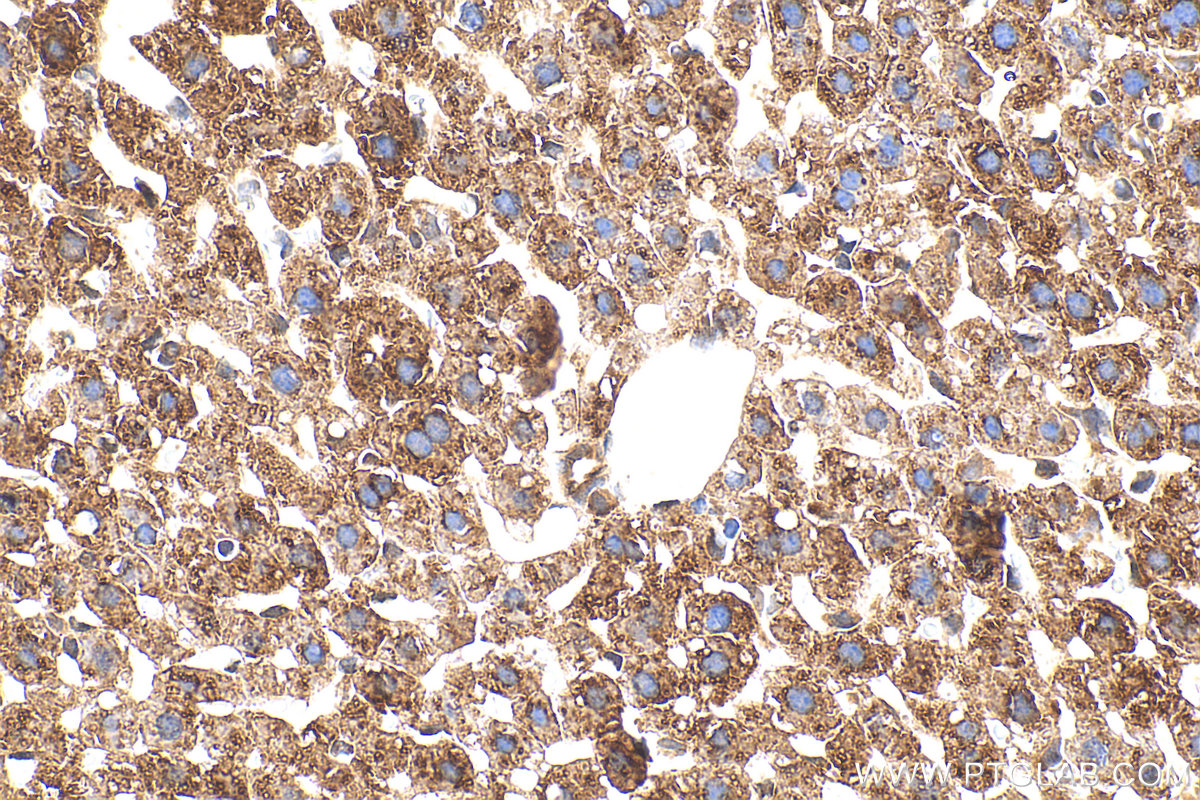

| Positive IHC detected in | mouse liver tissue Note: suggested antigen retrieval with TE buffer pH 9.0; (*) Alternatively, antigen retrieval may be performed with citrate buffer pH 6.0 |

| Immunohistochemistry (IHC) | IHC : 1:50-1:500 |